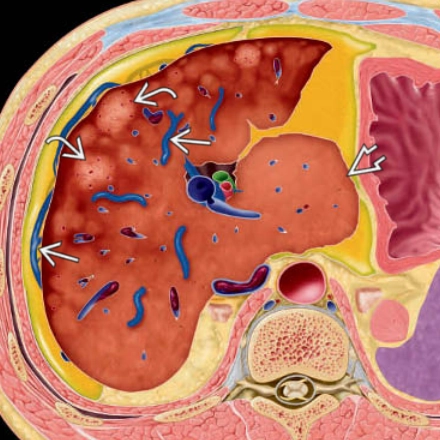

• Tăng áp lực tĩnh mạch cửa (Portal Hypertension)